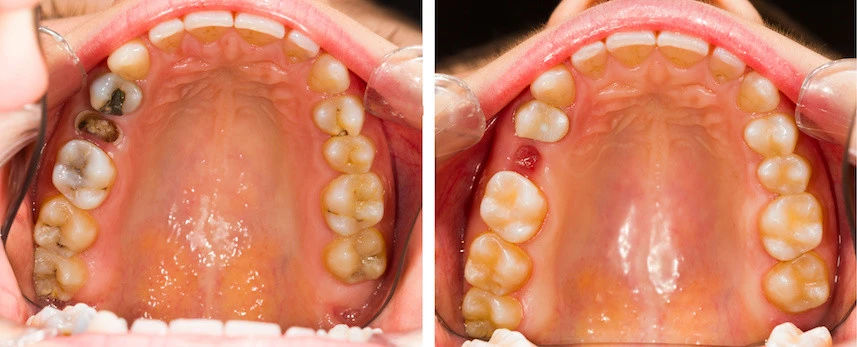

علاج الضرس المحفور الملتهب

علاج الضرس المحفور الملتهب يعتمد على شدة الالتهاب ومرحلة التسوس. في الحالات البسيطة، يبدأ العلاج بتنظيف التسوس جيداً ثم حشو الضرس لحمايته ومنع تفاقم المشكلة. إذا وصل الالتهاب إلى عصب الضرس، يجب إجراء علاج العصب عبر سحب العصب وتنظيف قنوات الجذر ثم حشوها، مما يخفف الألم ويمنع انتشار الالتهاب. بالإضافة للعلاج الطبي، يمكن تخفيف الألم مؤقتًا باستخدام مضادات الالتهاب والمسكنات التي يصفها الطبيب، وتطبيق كمادات باردة على الخد لتقليل التورم، وكذلك المضمضة بالماء الدافئ مع الملح أو استخدام زيت القرنفل كمسكن طبيعي. في الحالات المتقدمة جداً التي لا يمكن فيها إنقاذ الضرس.

قد يلجأ الطبيب إلى خلع الضرس من المهم زيارة طبيب الأسنان لتقييم الحالة بدقة والحصول على العلاج المناسب لمنع المضاعفات

علاج العصب ( الحشو العلاجي )

في حالة كان الالتهاب وصل للعصب يتم عمل حشو عصب الاسنان للمريض باستخدام تقنيات دقيقة تتوفر داخل مجمع الطب المتميز بالمدينة المنورة. حيث يقوم الطبيب بتنظيف القنوات الداخلية للضرس وإعادة حشوها بمادة طبية تمنع رجوع العدوى مرة أخرى للضرس.

فتح و تصريف الخراج

في حالة تكون خراج داخل الضرس واللثة يقوم الطبيب بفتحه وتصريف الصديد مع إعطاء المريض العلاج المناسب. مما يساعد على تخفيف التورم بشكل سريع.

خلع الضرس التالف

إذا استحال إنقاذه يتم خلع الضرس بطريقة آمنة باستخدام أحدث أجهزة الجراحة البسيطة. وكذلك توفير بعض البدائل مثل زراعة الأسنان المتاحة داخل مجمع الطب المتميز.